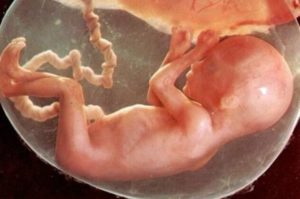

Сальные железы плода уже начали активно функционировать. Они продуцируют первородную смазку — специальное вещество, покрывающее тело малыша. Благодаря входящим в состав бактерицидным веществам, главной ее функцией является защита от воздействия околоплодных вод и патогенной микрофлоры.

На кожном покрове плода можно увидеть пушковые волосы — лануго. Их полное исчезновение произойдет после родов.

Кожа становится тоньше, а от пересыхания ее защищает специальная смазка. Кроха постоянно пьет амниотическую жидкость , поэтому мочится более 20 раз за сутки. Отходы его жизнедеятельности выводятся через почки будущей мамы.